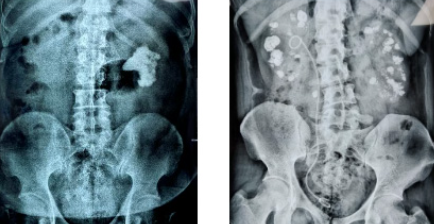

通过B超、CT扫描这些检查手段,能清晰看到这些肿块和正常组织的区别。绝大多数结节都是良性的,很少会变成癌症。医学统计显示,真正需要治疗的恶性结节比例非常低。

甲状腺超声检查不仅可以明确结节的部位、数目、大小、囊性还是实性、结节边缘是否清楚、结节内有无血管斑和微钙化等,还能辅助确诊甲状腺恶性肿瘤,如低回声、血运丰富、微钙化、形态不规则、淋巴结肿大。目前,高分辨的超声是甲状腺结节的首选检查。